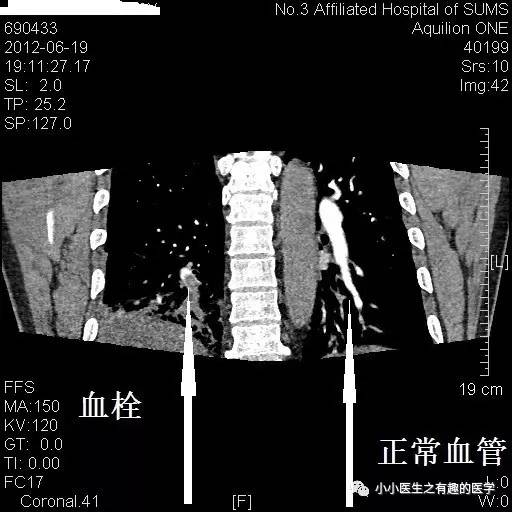

病例一:

女性,老年,胸痛伴气喘20余天。1周前出现双下肢浮肿。查体:双下肢足背浮肿。D-二聚体:5.10 ug/mL。心脏彩超:肺动脉收缩压RVSP:39mmHg。B超:双下肢深静脉血栓形成。

左肺动脉血栓。

左侧血栓,对比右侧就很通畅,一路顺风。